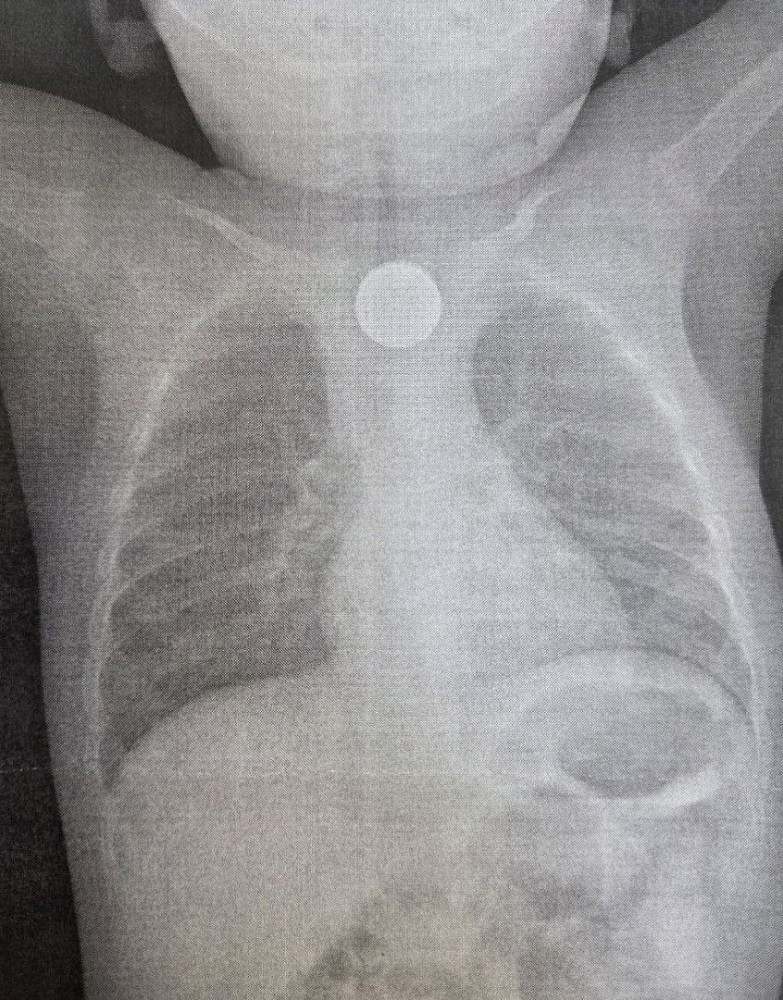

В Бурятии годовалый ребенок получил ожог пищевода 3 степени, проглотив дисковую литиевую батарейку и двухрублевую монету. Малыша спасли врачи ДРКБ.

Медики в составе врача-эндоскописта Зорика Хангалова, эндоскопической медицинской сестры Ларисы Никитиной и анестезиолога-реаниматолога Романа Цвикевича оперативно удалили монету и литиевую батарейку из пищевода при помощи внутрипросветной эндоскопии. Последний предмет вызвал химический ожог слизистой оболочки пищевода 3 степени, представляющий серьезную угрозу для жизни ребенка.

«В настоящее время состояние маленького пациента стабилизировано, он находится под круглосуточным наблюдением в отделении анестезиологии и реанимации. После дальнейшей стабилизации его переведут в профильное отделение», - рассказали в больнице.